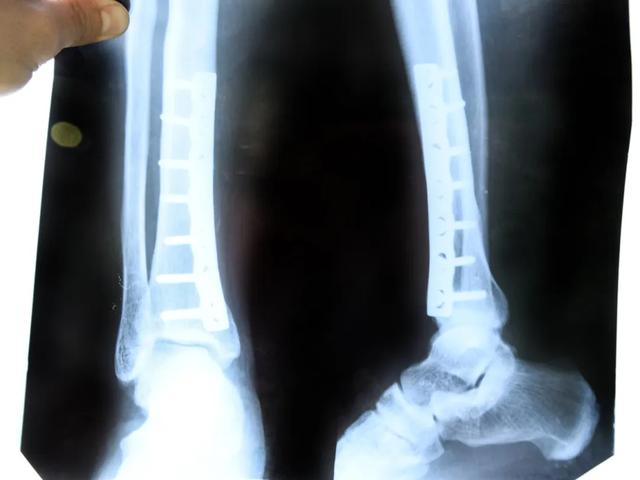

骨折手术后出现并发症:如伤口感染、内固定排异反应、骨髓炎等,需要及时取出内固定。

关节部位的钢板内固定:如肘关节、腕关节、膝关节、踝关节等,若内固定放置的位置影响关节活动,或固定的螺钉穿出关节面,此时内固定应及时取出,否则会造成关节畸形、关节活动障碍、疼痛等,甚至有发生创伤性关节炎的可能。